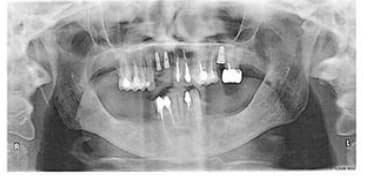

la par exemple je vois pas ce que c'est sensé représenter...